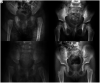

Figure 2.

Radiographic example for both closed (A, B) and medial open (C, D) reduction. Both patients underwent initial surgery at 6 months. Favorable radiologic outcomes were obtained during the 4-year follow-up.